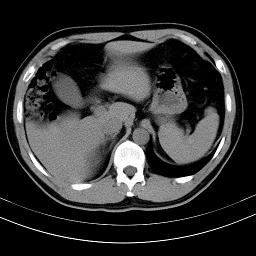

标题: CT18388:肝脏膈肌间隙内大量脂肪密度影 [打印本页]

标题: CT18388:肝脏膈肌间隙内大量脂肪密度影

是脂肪不是气体,有时候会碰到这样的病人,脂肪过多吧。

腹腔脂肪沉积过多

膈下脂肪沉积。

考虑膈下脂肪沉积。

激素治疗的病人容易脂肪沉积